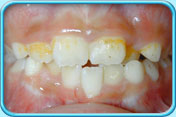

牙齒表面有啡黃或白斑

初期蛀牙

牙科醫生可於牙齒表面塗上牙面氟化物劑,使初期蛀牙得以修復

牙齒發育時受感染或氟斑牙

以複合樹脂補牙、做貼面修復治療或鑲配人造牙冠

填上複合樹脂後的牙齒